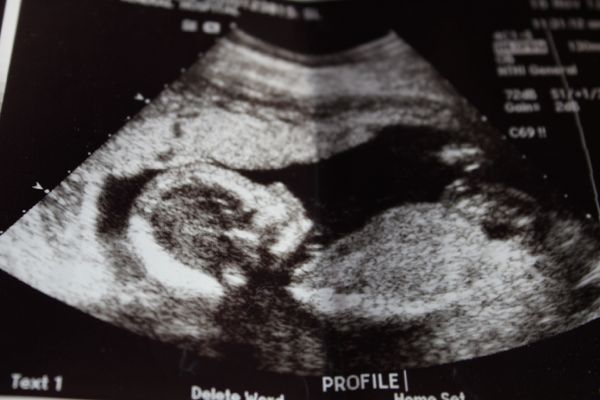

We are having a baby!!

I am now 24 weeks pregnant and everything has been going great. I think feeling the baby move is one of the freakiest/coolest things ever! We found out we were having a boy and that made it even more real. A baby boy! Wow.